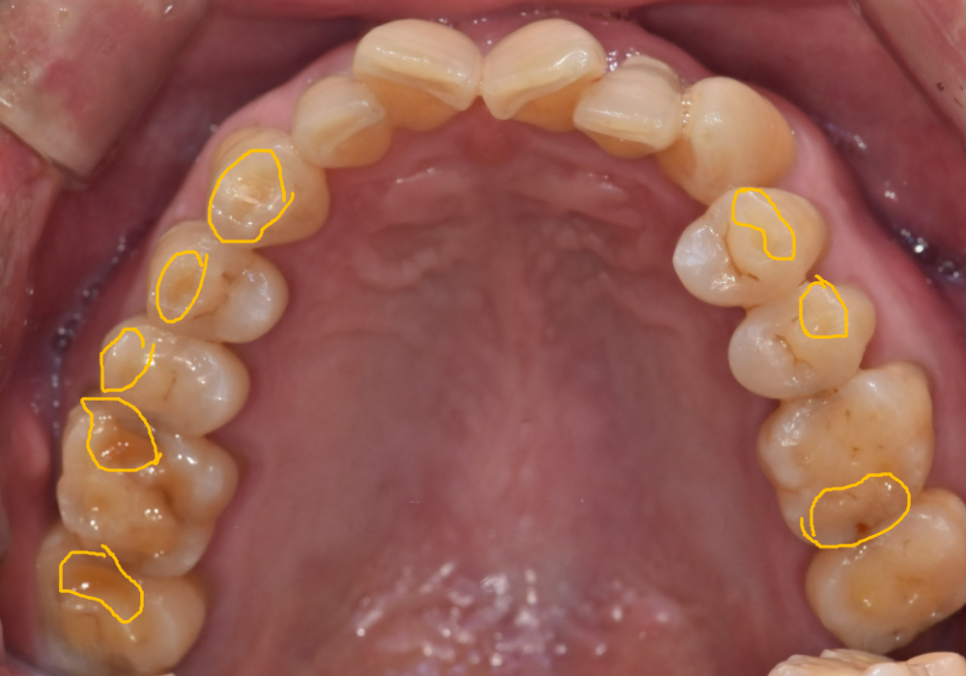

입안을 살펴보니 전체적으로

치아가 많이 닳아 있었고,

평소 얼음을 잘 깨 드실 만큼

치아를 강하게 써오신 습관이 있으셨습니다.

정밀 CT를 통해 분석해 보니,

치아에 금이 가 있는게 보입니다.